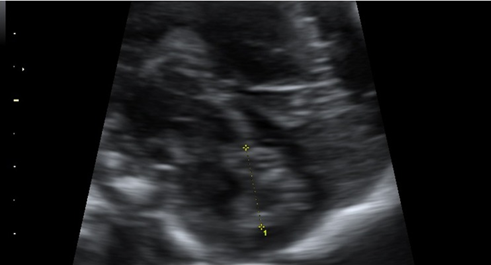

Kivilevitch et al., The Normal Fetal Pancreas, J Ultrasound Med 2017; 36:1997–2005

Beispiel Pankreasumfang

Tabelle Pankreasumfang